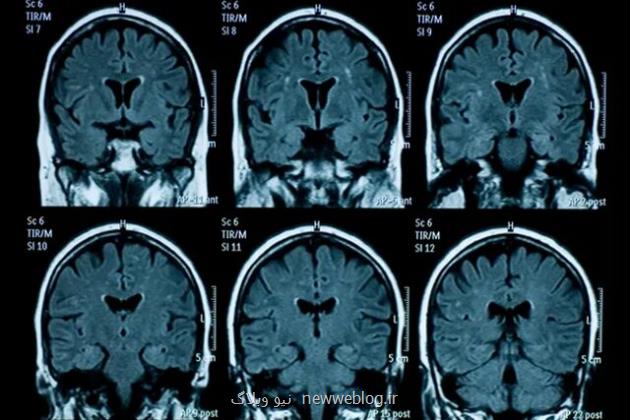

محققان اسکن های مغز ۸۱ نوجوان در ایالات متحده آمریکا را که قبل از وقوع همه گیری، بین نوامبر ۲۰۱۶ تا نوامبر ۲۰۱۹ ثبت شده بود، با اسکن مغزی ۸۲ نوجوانی که اسکن مغز آنها بین اکتبر ۲۰۲۰ تا مارس ۲۰۲۲ در طول همه گیری و بعد از لغو قرنطینه جمع آوری شده بود، مقایسه کردند.

بعد از تطبیق ۶۴ شرکت کننده در هر گروه با در نظر گرفتن عواملی همچون سن و جنسیت، محققان دریافتند که تغییرات فیزیکی که در دوران نوجوانی در مغز رخ می دهد همچون نازک شدن قشر و رشد هیپوکامپ و آمیگدال، در دوران بعد از قرنطینه در گروهی که اسکن آنها بعد از همه گیری ثبت شده بود نسبت به گروه دیگر بیشتر بوده است. این نشان داده است که چنین فرآیندهایی سرعت گرفته یا به عبارت دیگر، مغز آنها سریع تر پیر شده است.

یان گوتلیب(Ian Gotlib)، استاد روانشناسی در دانشگاه استنفورد و نویسنده اصلی این مطالعه می گوید: تفاوت سنی مغز(میان این دو گروه) حدود سه سال بود و با عنایت به این که طول قرنطینه کمتر از یک سال بود، انتظار افزایش زیادی نداشتیم.